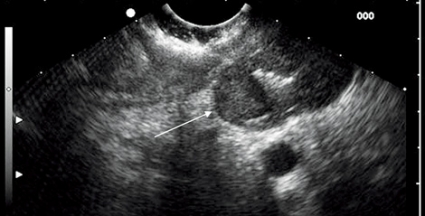

Den vanligaste submukösa tumören är gastrointestinal

stromacellstumör (GIST), som utgår ifrån muscularis propria eller muscularis mucosae (Figur 4). Vid storlek >3 cm, oregelbundna kanter och heterogen ekogenitet ökar risken för malignitet, men det kan vara svårt att skilja mellan benign och malign GIST endosonografiskt, och då kan man ta vävnadsprov med EUS-FNA eller vävnadsbiopsi för cytologisk analys av mitotiskt index. Immunhistokemisk analys hjälper inte bara till med diagnostiken av GIST, utan underlättar också differentialdiagnostiken mot andra ovanligare tumörer såsom leiomyom, leiomyosarkom och schwannom. En diagnostisk markör för GIST är c-Kit (CD117), medan desmin och S-100-protein är vanligare uttryckt i leiomyom, leiomyosarkom och schwannom.